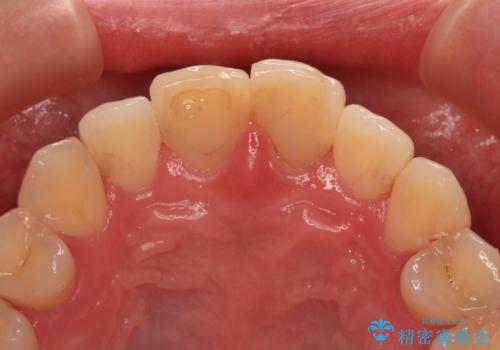

変色した前歯 オールセラミッククラウンにより審美歯科治療

- 神経を取り除いたことで経年変色した前歯2本を気にして来院された患者様です。

根管治療を行う必要はないと判断し、双方の歯にグラスファイバーを含有した土台を植立してオールセラミッククラウンにて補綴することとしました。

色調が周囲の歯とアウトともに、表面のつぎはぎや穴を封鎖した際の段差などが解消され、天然歯のような感触となりました。